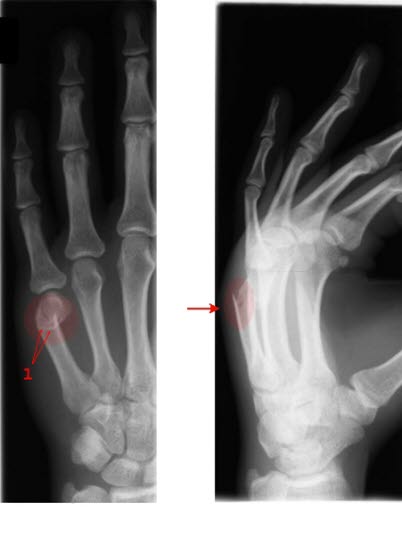

Metacarp 5 fraktur

Tverrfraktur femte metacarp (pil)

Typisk fraktur etter slag mot hardt objekt, vegg eller hake